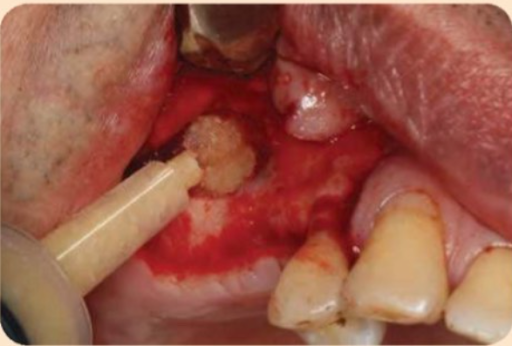

Có nhiều loại vật liệu xương ghép có thể được sử dụng để nâng xoang. Xương tự thân vẫn được xem là chuẩn vàng của vật liệu ghép nhờ hàm lượng protein tạo hình thái xương (BMPs) cao và khả năng biệt hóa các tế bào từ mô xung quanh thành tế bào xương.

Tuy nhiên, các nghiên cứu lâm sàng cũng đã chứng minh được kết quả thành công của ghép đồng loại, ghép dị loại, và vật liệu tổng hợp. Điểm khác biệt của những vật liệu ghép này là chúng bị hấp thu chậm hơn so với xương tự thân. Một nghiên cứu đã cho thấy khi thêm một lượng nhỏ xương tự thân vào xương ghép dị loại thì sẽ tăng sự tạo xương sống.

Bằng chứng trong y văn dường như cho thấy quy trình ghép tốt nhất là hỗn hợp xương hạt tự thân với xương bò khoáng khử khoáng hoặc xương ghép đồng loại khử khoáng đông khô. Tỷ lệ tồn tại của implant bề mặt nhám sử dụng quy trình ghép này là khoảng 96.8-99.8%. Bằng chứng hiện này còn cho thấy ghép xương hạt cho kết quả tốt hơn ghép xương khối. Wallace và Froum đã báo cáo tỷ lệ thành công 80.40% của implant bề mặt nhám được đặt vào xương ghép khối so với 94.83% của xương ghép hạt. Ngoài ra, BMP-2 và -7 tái tổ hợp của người có thể cải thiện kết quả sau cùng bằng cách làm tăng lượng xương hình thành nhờ tính chất cảm ứng xương của chúng (Hình dưới đây).